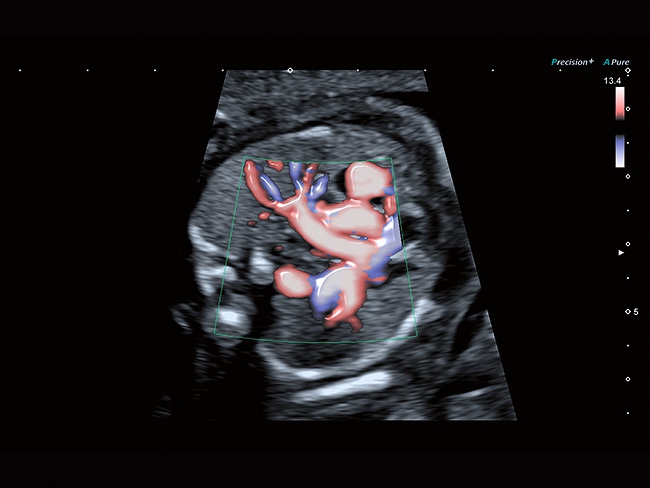

Aplio a550 может работать с линейным матричным датчиком и поддерживает новейшие монокристаллические датчики. Также Aplio a550 поддерживает большое количество дополнительных опций, таких как - SMI, Компрессионная эластография, Эластография сдвижной волны, Smart Fusion, исследования с использованием контраста (CEUS), 3D реконструкции в реальном времени (4D), функции автоматической оценки подвижности миокарда и фракции выброса.

Трехмерная реконструкция ЦДК:

Да